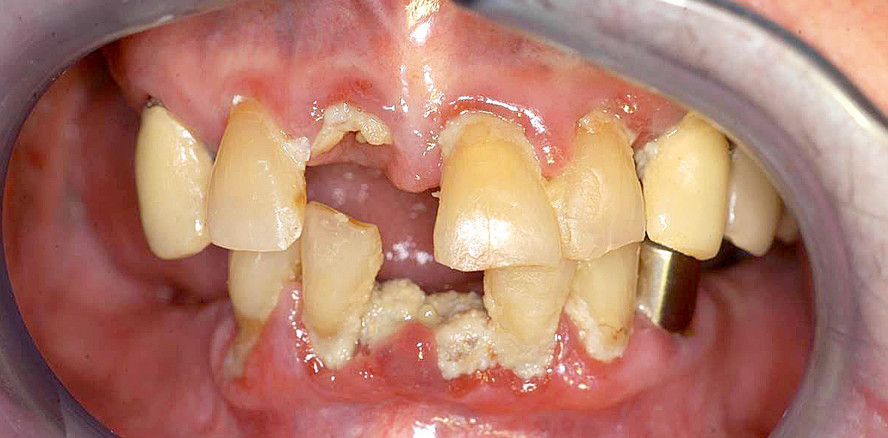

Karies bei Störungen der Speichelsekretion

Zu den charakteristischen Problemen bei Allgemeinerkrankungen (wie Diabetes) oder bestimmten Medikationen (z. B. blutdrucksenkende oder antidepressive Medikamente und bestimmte Psychopharmaka) gehören kariöse Läsionen an Glattflächen sowie die Wurzelkaries. Häufig treten diese in Verbindung mit einer verminderten Speichelsekretion (Xerostomie) auf. Als Folge der fehlenden protektiven Wirkung des Speichels entwickeln sich kariöse Läsionen bei Xerostomiepatienten 15-mal so schnell wie bei gesunden Kontrollpersonen.12 Die rasche Progredienz ist durch die fehlende Pufferkapazität des Speichels zu erklären. Bei nachlassender Remineralisationsfähigkeit und gleichzeitig steigenden Plaqueansammlungen können Demineralisationen vermehrt an sonst wenig kariesanfälligen Flächen entstehen (Abb. 1a–c).13

Gingivale Wucherungen

Als Folge einer antihypertonen Therapie mit Kalziumkanalblockern (Nifedipin), immunsuppressiven Medikamenten (Ciclosporin A) oder bei einer Medikation mit bestimmten Psychopharmaka (trizyklische Antidepressiva, Hypnotika und Sedativa) können bei den dafür empfänglichen Patienten gingivale Veränderungen (Wucherungen) auftreten. In fortgeschrittenen Fällen können diese die Durchführung der Mundhygiene und Therapie von kariösen Defekten in unmittelbarer Nähe der Gingiva erschweren (Abb. 1a und 3a).9

Therapie gingivaler Wucherungen

Die im Verlauf einer antihypertonen oder antikonvulsiven Arzneimitteltherapie auftretenden gingivalen Wucherungen werden zunächst konservativ durch eine supra- und subgingivale Belagentfernung behandelt (Abb. 1a–c, 3a und b). Erst wenn nach wiederholten professionellen Zahnreinigungen mit Mundhygieneanweisungen weit ausgedehnte, medikamentös induzierte, gingivale Wucherungen die Kaufunktion beeinträchtigen und eine Zahnpflege erheblich erschweren, ist eine chirurgische Reduktion durch eine Gingivektomie und Gingivoplastik unumgänglich.